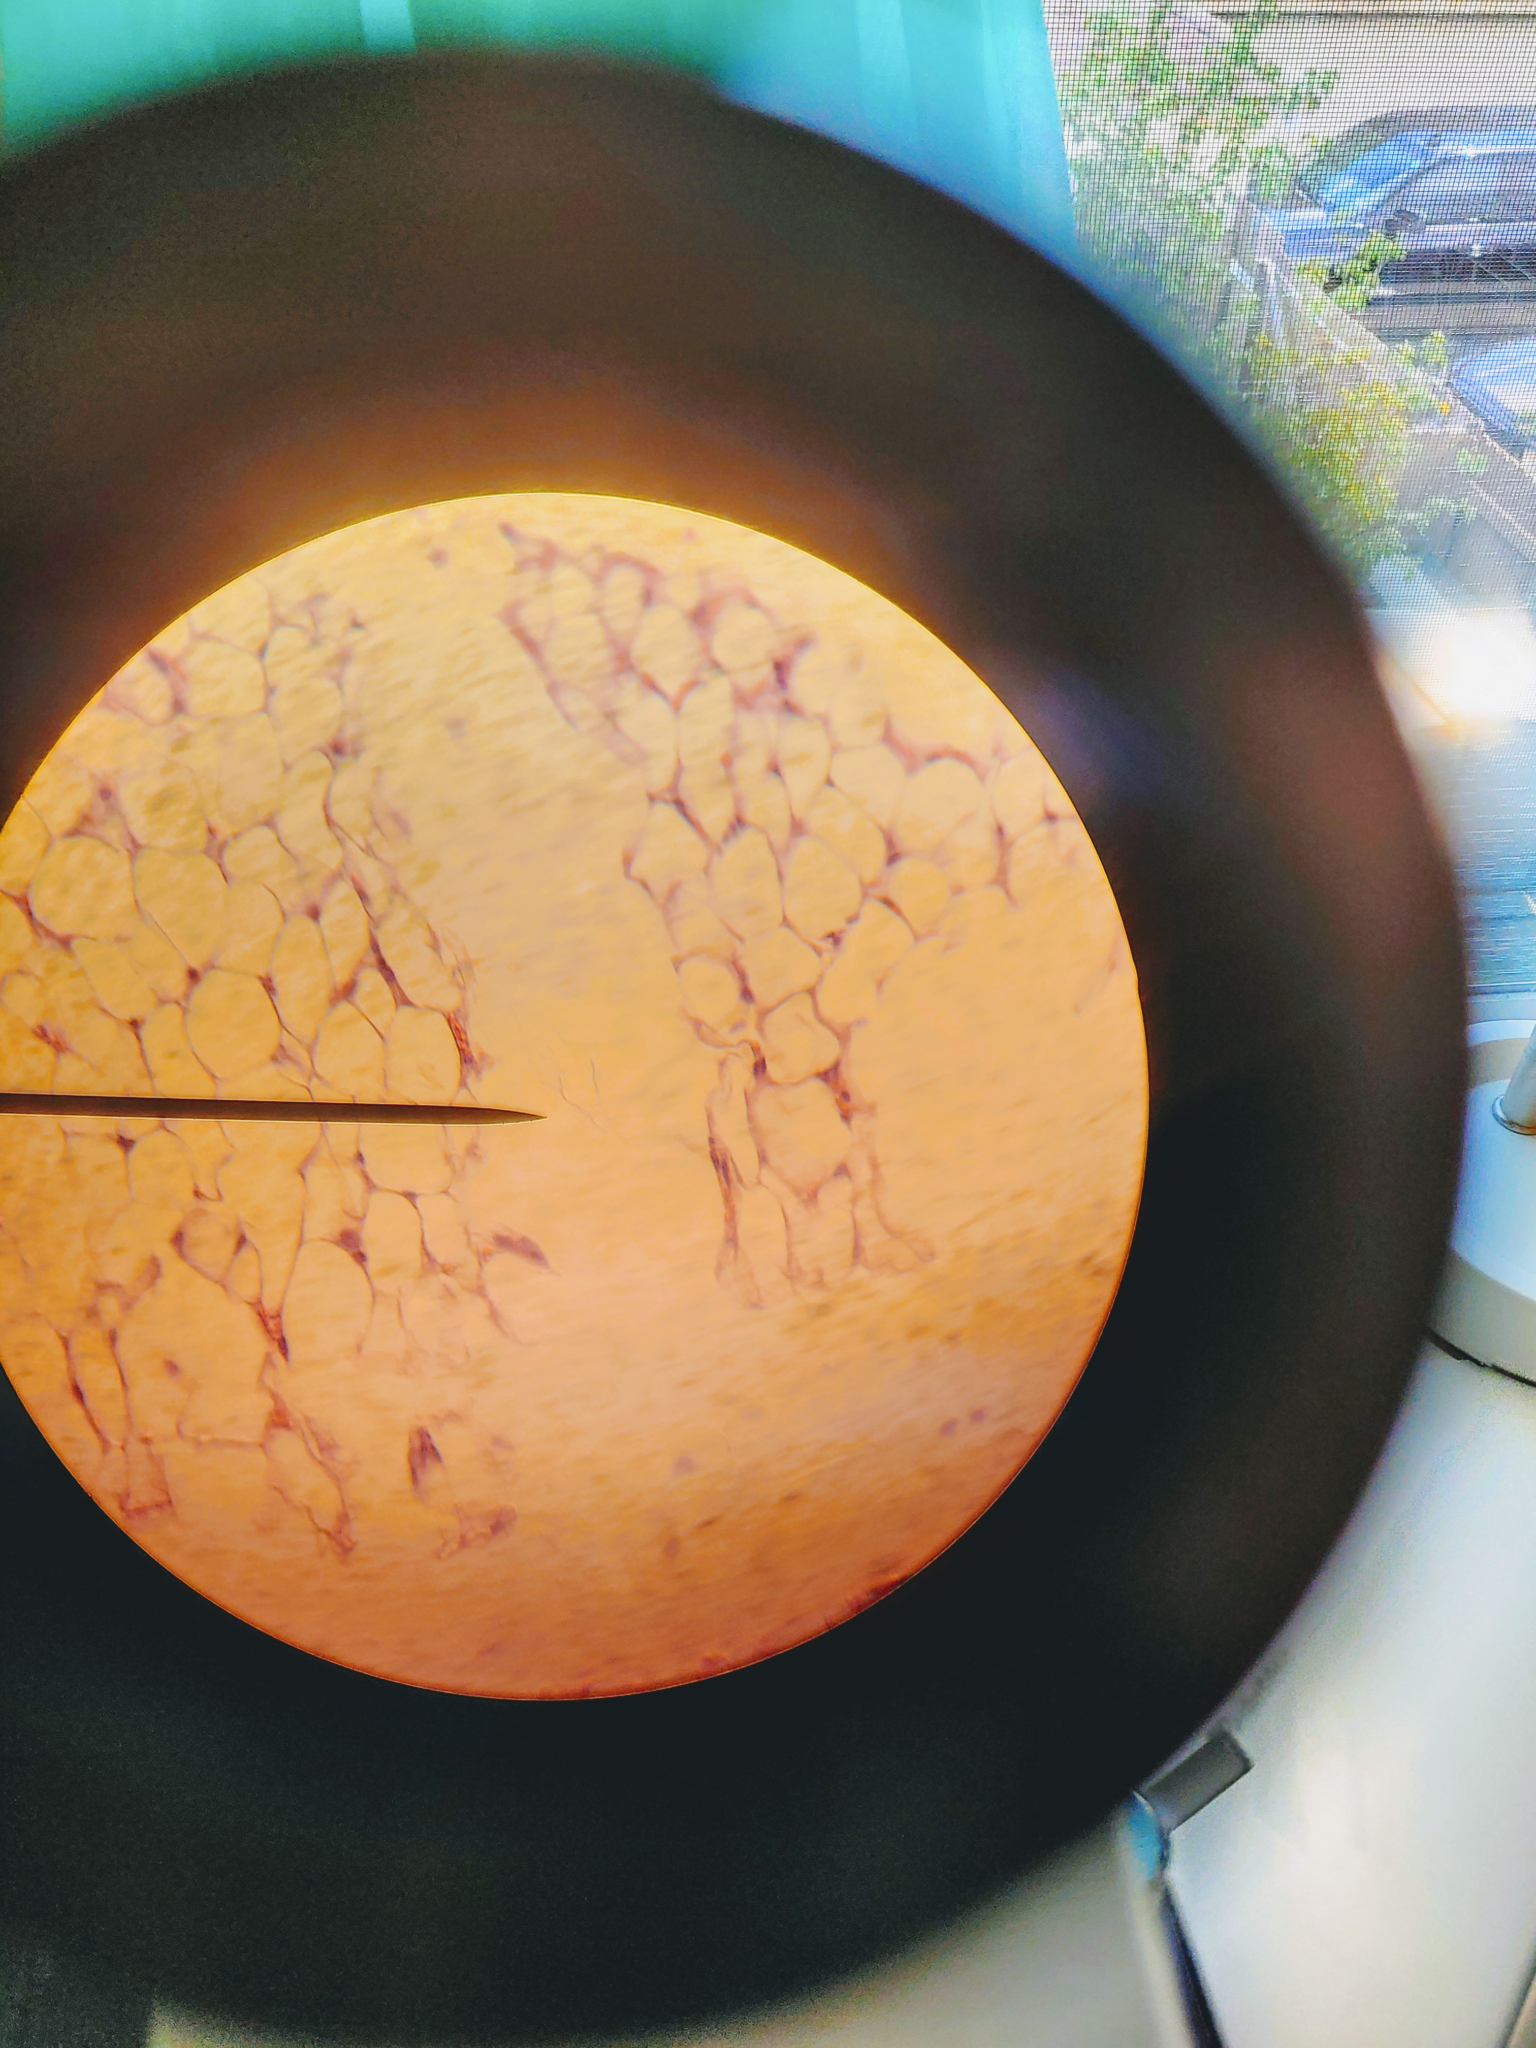

The big whitish open areas of the tissue are called the adipose tissue. This tissue also has fats ( which are the purple dots in the adipose tissue ) which are called the nuclei. Another major feature of the adipose tissue would be the cytoplasmic membrane which is the strands that are connected to the nuclei which form the adipose cells.

FUN FACT: Adipose tissue can comprise cell containing fat and oil.